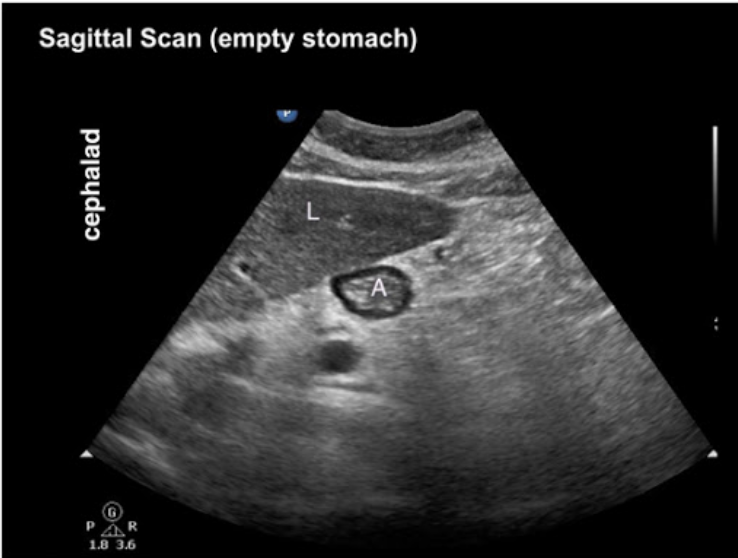

20.1 The structure labelled A shows

a. Empty stomach